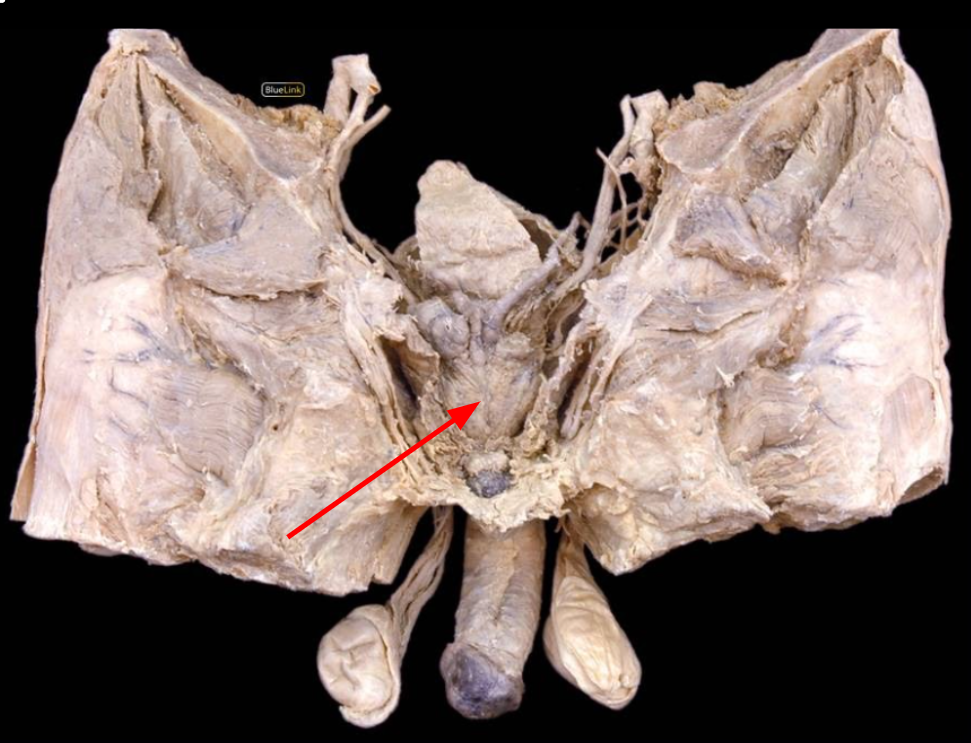

Prostate

Pudendal Nerve